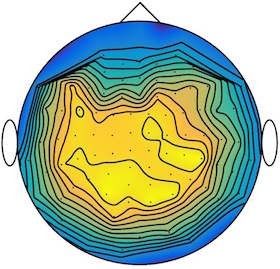

We applied our method to a magnetoencephalography (MEG) dataset. In this setup, brain activity of a subject is recorded (Elekta Neuromag, 306 sensors of which 204 planar gradiometers and 102 magnetometers, sampling frequency 1000Hz) while the subject reacted to the presentation of a target stimulus by pressing either the left or the right button.

Data is preprocessed applying signal space separation correction, interpolation of noisy sensors, and realignment of data into a subject-specific head position (MaxFilter, Elekta Neuromag). The signal was then filtered (low pass 40HZ), and artifacts such as blinks and heartbeats removed thanks to Signal-Space Projection using the Brainstorm software222http://neuroimage.usc.edu/brainstorm. The samples we used for our barycenter computations are an average of the norm of the two gradiometers for each channel from stimulation onto 50ms and the classes were left or right button.

| Class 1 | Class 2 | ||||||

|

|

|

|

|

|

|

|

| Sample 1 | Sample 2 | Sample 3 | Mean | Sample 1 | Sample 2 | Sample 3 | Mean |

|

|

|

|

|

|

|

|

This results in two classes of recordings, one for each pressed button. We aim at computing a representative activity map for each class using Wasserstein barycenters. For each class we have recordings each having samples located on the vertices of an hexahedral mesh of a hemisphere (corresponding to a MEG recording helmet). These recorded values are positive by construction, and we rescale them linearly to impose . Figure 6, top row, shows some samples from this dataset, displayed using interpolated colors as well as iso-level curves. The black dots represent the position of the electrodes on the half-sphere of the helmet, flattened on a 2-D disk.

We computed TV-regularized barycenters independently for each class by solving (16) with the TV regularization using the projected gradient descent method (22). We used a squared Euclidean metric (24) on the flattened hemisphere. Since the data is defined on an irregular graph, instead of (23), we use a graph-based discrete gradient. We denote the graph which connects neighboring electrodes. The gradient operator on the graph is

The total variation on this graph is then obtained by using , the norm, i.e. we use in (23).

Figure 6 compares the naive barycenters (i.e. the usual mean), barycenters obtained without regularization (i.e. ) and barycenters computed with an increasing regularization strength . The input histograms being very noisy, the use of regularization is important to make the area of significant activity emerge from the noise. The use of a TV regularization helps to keep a sharp transition between active and non-active regions.